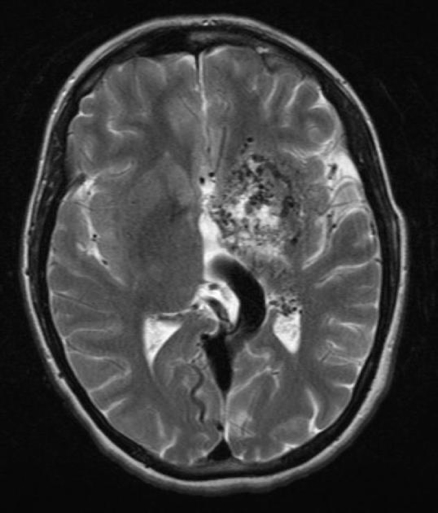

Intracerebral Haemorrhage

Aetiology

- Hypertension (most common)

- AV malformations, trauma, bleeding diathesis

Pathogenesis

- Bleeding into brain parenchyma

- Leads to mass effect, ↑ICP, and ischaemia

Morphology

- Slit haemorrhages in chronic HTN

- Lacunar infarcts in brainstem/basal ganglia

Clinical Features

- Acute headache, vomiting, meningism

- Nystagmus, anisocoria, focal neurological deficits

- Signs of raised ICP and possible brain herniation

- Altered consciousness

Investigations

- CT/MRI Brain: Confirms haemorrhage

- Transcranial Doppler: Assess AVMs